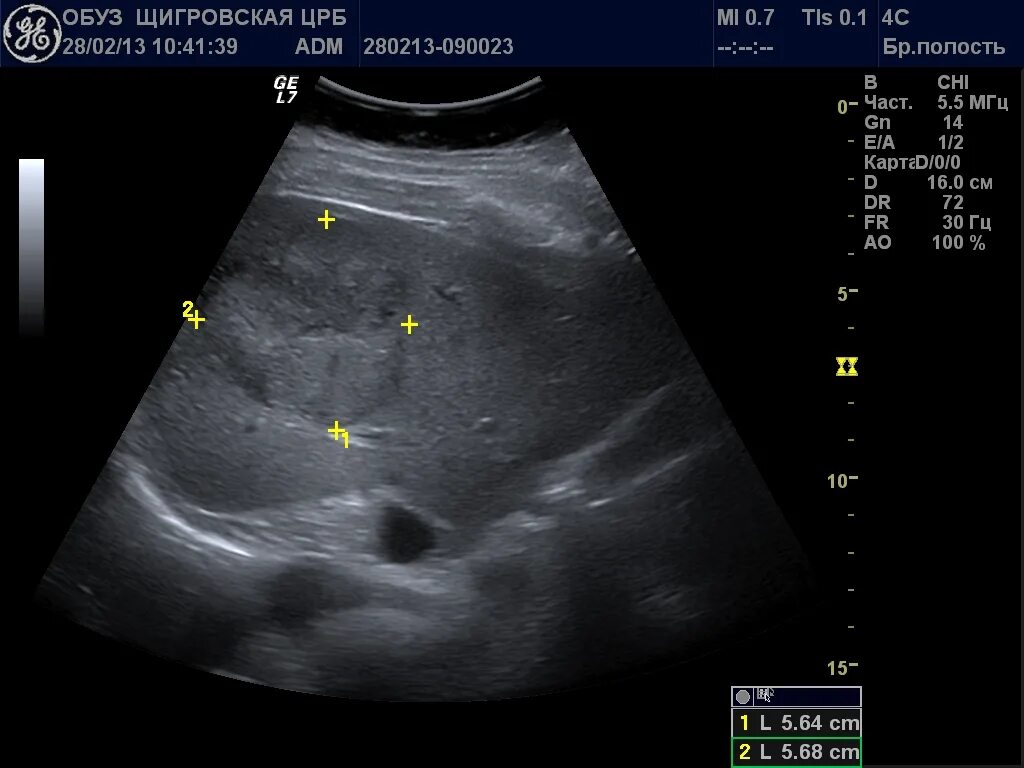

Подготовка к узи печени у взрослых